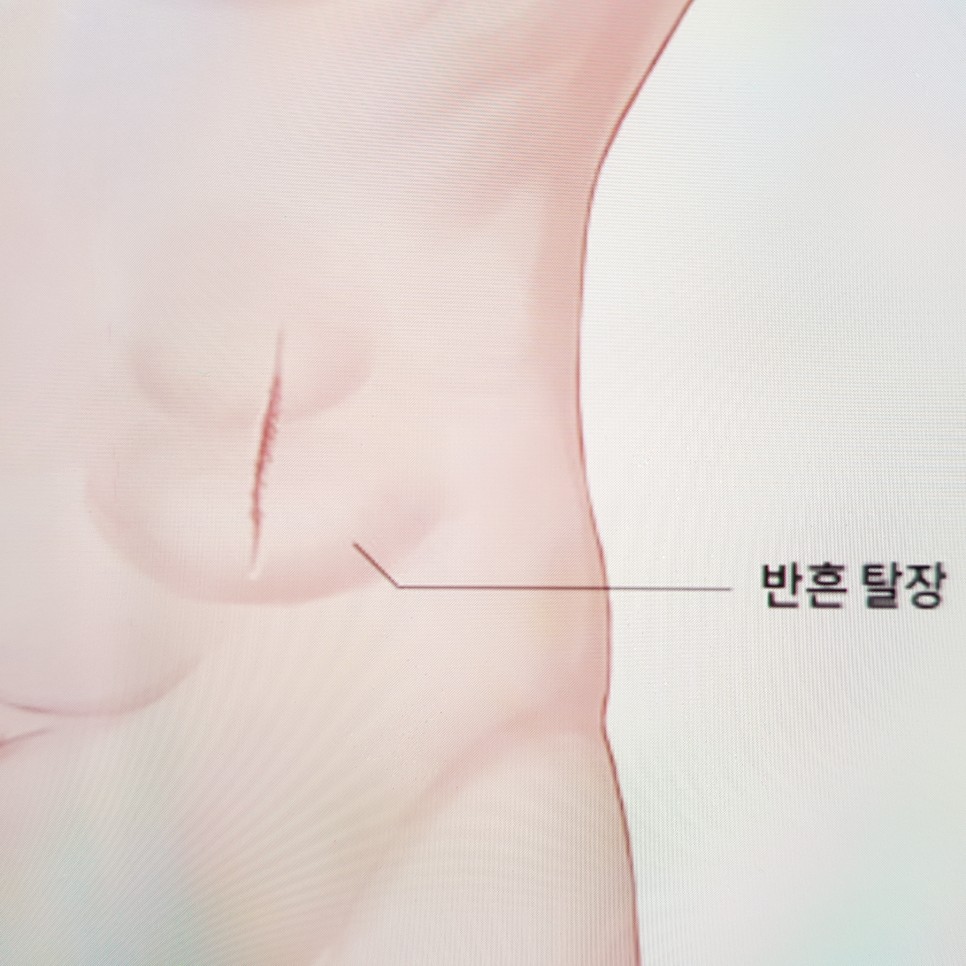

상처 부위, 수술 부위에서 튀어나온 경우 절개 탈장, 배꼽 부분에서 튀어나왔을 경우 배꼽 탈장, 가장 많이 발생하는 탈장이 서혜부에서 발생하는 서혜부 탈장입니다.